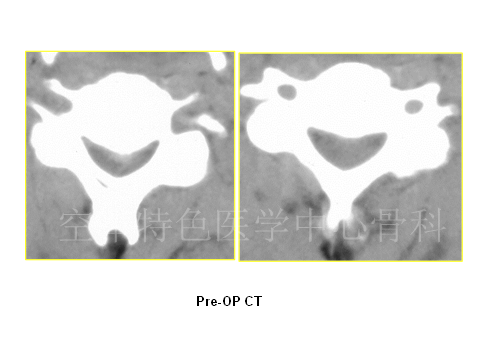

患者男性,37岁,主诉:头颈部不停抽动11年,四肢麻木无力,行走不稳 1月余。既往曾以“共济失调”入住神经内科。查体:颈3平面以下痛觉减退,双肘关节以下痛觉减退明显,胸4平面以下感觉减退。四肢肌力Ⅳ级,四肢腱反射活跃,肌张力高。双侧Hoffman’s征+,Babinski’s征+。JOA评分:9分。患者入院时头颈部不自主的扭动,行走不稳,易摔跤。

患者影像学资料如下: